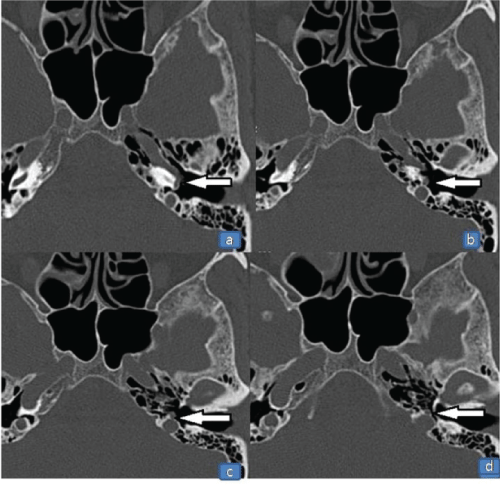

A 50-year-old woman presented with a four-year history of left-sided pulsatile tinnitus and hearing impairment. Otoscopy revealed a reddish mass behind the inferior half of the left tympanic membrane. Audiometric evaluation showed mild conductive hearing loss in the left ear. High-resolution CT scanning of the temporal bone was performed. On the CT scan of the temporal bone, a left-sided aberrant ICA entering the middle ear cavity through an enlarged inferior tympanic canaliculus was observed (Figure 1). The right temporal bone was normal. MRA showed a reduced diameter and lateralization of the left ICA (Figure 2A and Figure 2B). The vertical segment of the ICA was lateral and posterior to a line drawn vertically through the vestibule. Hypoplasia of the A1 segment of left ACA was also identified.

Figure 1: Axial high resolution computed tomography scan of the temporal bone, showing left aberrant internal carotid artery entering the middle ear cavity through an enlarged inferior tympanic canaliculus (arrows).

The misdiagnosis of aberrant ICA can result in fatal bleeding or other life-threatening complications. Suspicion of a retro-tympanic mass in the middle ear necessitates radiographic investigation. CT scan of the temporal bone is considered as one of the most reliable methods to diagnose an aberrant ICA. On CT scan, aberrant ICA is recognized by; an enhanced mass in the hypotympanum, a deficient bony plate along the tympanic portion of the ICA, absence of the vertical segment of the carotid canal, and a reduced diameter of ICA that runs adjacent to the jugular bulb [2-5]. MRA can be used as an additional tool for the definitive diagnosis and it also provides excellent visualization of the intracranial and extracranial circulation. The important features at angiography are; a reduced diameter of the tympanic ICA, the vertical segment of the ICA is lateral to a line drawn vertically through the vestibule [2,5]. In our case, CT and MRA showed all the characteristic features of aberrant ICA. In addition, hypoplasia of the A1 segment of the anterior cerebral artery was identified on MRA. In a review of the literature, we noted various other reports of an aberrant ICA in which hypoplasia of the A1 segment of the ACA was noted as an incidental finding [8-11]. Hypoplasia of the A1 segment of the ACA is reported to be present in 10% of autopsies [12]. The relationship between ipsilateral absence or hypoplasia of the A1 segment and a reduced caliber of the ICA has been further reported by Kane et al. [13] in a study of intracranial MR angiograms.